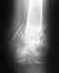

Re: Кость так и не срастается